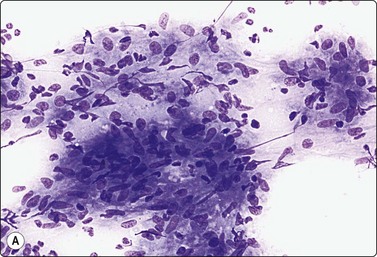

image image image

Fig. 5.40 Mantle cell lymphoma

(A) Nuclei a little larger than those of lymphocytes irregular shape, finely granular chromatin without distinct nucleoli. A few normal lymphocytes present. (B) Central histiocyte for size comparison (C) Immunostaining with CD5: strongly positive reactive T cells and moderate positivity in malignant lymphoma cells (A, MGG, HP; B,Pap HP; C immunostain CD5, IP).

Mantle cell lymphomas are generally clinically aggressive neoplasms, usually high stage at the time of presentation: generalized lymphadenopathy, splenomegaly, bone marrow and blood involvement. One must be wary of some uncommon variants (pleomorphic, small round cell, marginal zone-like) which may overlap with other lymphoma subtypes.69 The small cell variant appears to have a more indolent course. Immunostaining for Cyclin D1 on cytospin preparations can be unreliable.

Mantle cell lymphoma (MCL) (Fig. 5.40)143,150,151

Usually in adults over 50 years of age

Criteria for diagnosis

1 monotonous population of small centrocyte-like cells with occasional histiocytes,

2 blastoid variant cells resemble lymphoblasts,

3 immunophenotype: CD19, CD20, SIg, CD5, FMC7, Cyclin-D1 (cell block or CNB); CD10 and CD23 negative,

4 aberrant immunophenotype: CD5 negative, CD5 and CD10 positive, CD23 weakly positive,19,20,69

5 genetics: t(11;14) almost all cases.